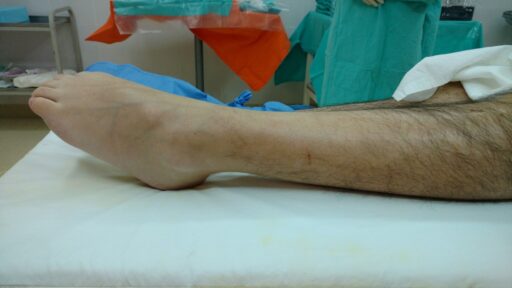

Artropatia diabetica

La diabetes puede causar artropatía, una afección que daña las articulaciones debido a altos niveles de azúcar en sangre, afectando la movilidad y bienestar general.